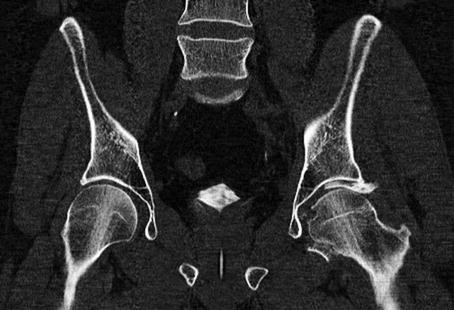

This pelvic coronal CT image identifies a displaced posterior wall fracture fragment that is located between the femoral head and acetabular dome causing a nonconcentric reduction. This was one of five separate displaced posterior wall fracture fragments that were noted to be within the joint. An open reduction was indicated and performed urgently. The displaced fracture fragments were first removed from the hip joint so the femoral head could be congruent with the acetabular dome. Then the individual fragments were reduced and stabilized with two supporting plates